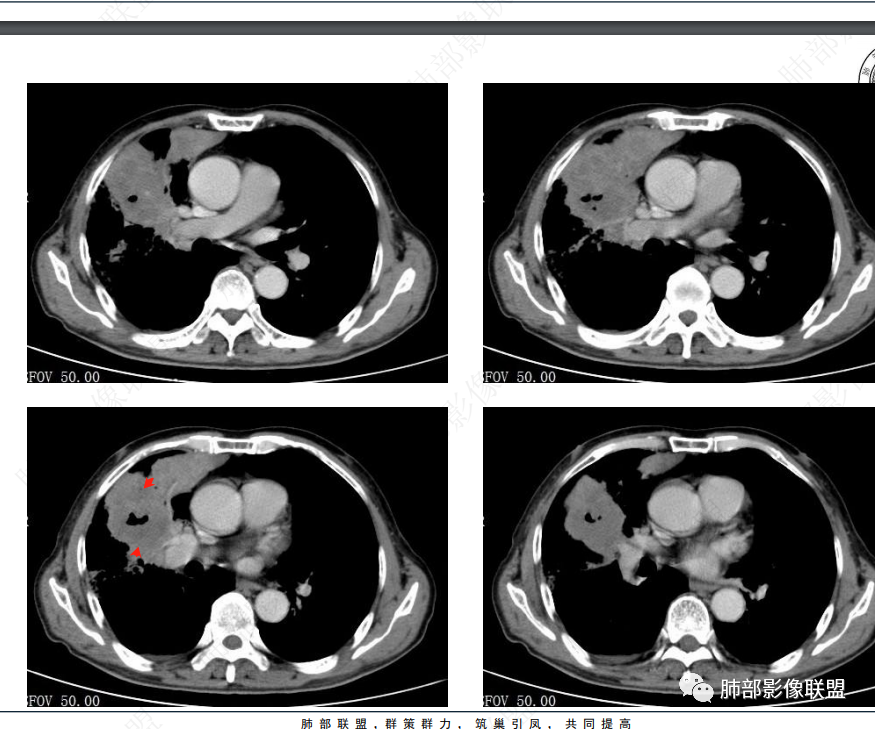

右肺上叶实变,宽基底与胸膜相连,邻近胸膜积液,上叶支气管阻塞,不均匀强化,血管显示可,局部坏死环形强化,可见气泡,考虑慢性炎症伴脓肿,放线菌?鉴别腺癌

右肺上叶尖段大片状实变,近肺门侧支气管闭塞,并可见病灶内部有片状液化坏死区,有空泡气体,病灶紧贴胸膜,胸膜反应性增厚,伴有少见积液,增强扫描内部不均匀强化,血管走形正常。影像符合慢性化脓性感染。

右肺上叶大片实变影,内密度不均匀,可见坏死环形强化,支气管被粘液栓阻塞,首先考虑感染性病变,奴卡?放线菌感染?

右肺上叶大片实变,密度不均,近端环形强化并见空泡,病灶与胸膜广基相连,之间并可见积液,考虑放线菌,鉴别腺癌

晨读:右肺上叶实变,密度欠均匀,不均匀强化,内血管走形可,近端环形强化并见空泡,考虑放线菌可能,鉴别腺癌

右肺上叶实变,宽基底与胸膜相连,不均匀强化,血管显示可,局部坏死环形强化,可见气泡,考虑慢性炎症伴脓肿,放线菌?鉴别腺癌

右主支气管周围多发淋巴结肿大融合(提示右主支气管有外受压变窄),右肺上叶尖前不张,内见支气管粘液栓和坏死及环形强化特点,邻近胸膜增厚及右肺上叶后段支气管扭曲及狭窄后扩张,周边索条纤维化,综合TB表现,超声支气管镜检查。

老年女性患者胸痛咳嗽半年多时间。右肺上叶大片状实性病灶,近端支气管受压变窄。病灶内部密度不均,伴有不均匀强化,有局灶坏死,以及有支气管造影征,胸膜面显示不行,伴有少量的积液,病灶有局部的膨胀,纵隔淋巴结增大。

老年女性患者胸痛咳嗽半年多时间。右肺上叶大片状实性病灶,近端支气管受压变窄。病灶内部密度不均,伴有不均匀强化,有局灶坏死,以及有支气管造影征,胸膜面显示不清,伴有少量的积液,病灶有局部的膨胀,纵隔淋巴结增大。

右肺门结节,显著强化,内可见坏死及悬浮气泡,远端阻塞性肺不张,心脏纵隔右移,结节及不张内血管影走行自然,并可见粘液拴,隆突下淋巴结肿大,慢性病程,病变跨叶,首选感染性病变放线菌感染,其次鉴别腺癌

晨读:右肺上叶大片状实变影,血管走形自然,可见类圆形低密度区,其内可见气泡影,纵膈内可见肿大淋巴结显示。考虑慢性炎症并脓肿形成,放线菌可能。鉴别淋巴瘤、腺癌。